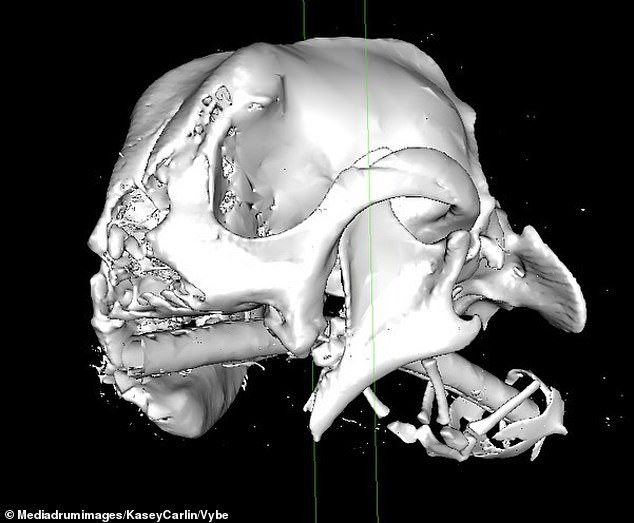

A puppy named Millie, who faced a rough start to life, has found a loving home after a transformative operation. Just one year old, Millie lost her snout due to a brutal attack but now has a fresh start.

Before her surgery, Millie’s large tongue hung down from her damaged snout, as seen in images shared by her new owner, Kasey Carlin.

Known affectionately as “spotty mop” by Kasey, Millie began life as a stray on the streets of Russia. Animal activists found her with severe injuries, likely caused by someone deliberately stomping on her face.

When rescued, she was trying to scrape the decaying material off her face with her paws.

Since arriving in the UK a little over a month ago, Millie has had more surgeries to help her live a more normal life. Her damaged right eye was removed, and a prosthetic added.

Kasey believes Millie’s injuries could have been caused by being used as target practice, though they might also have been a failed attempt at euthanasia.